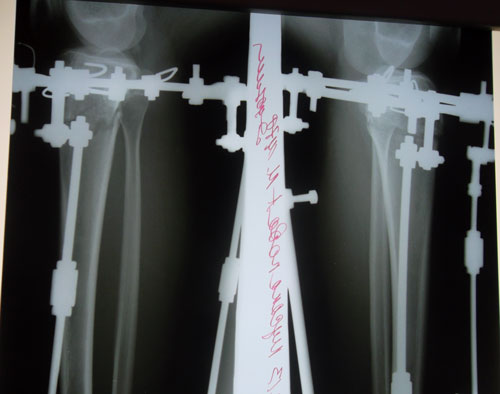

Ножки на 41-й день с момента операции.

рентген в 41 день с момента операции.